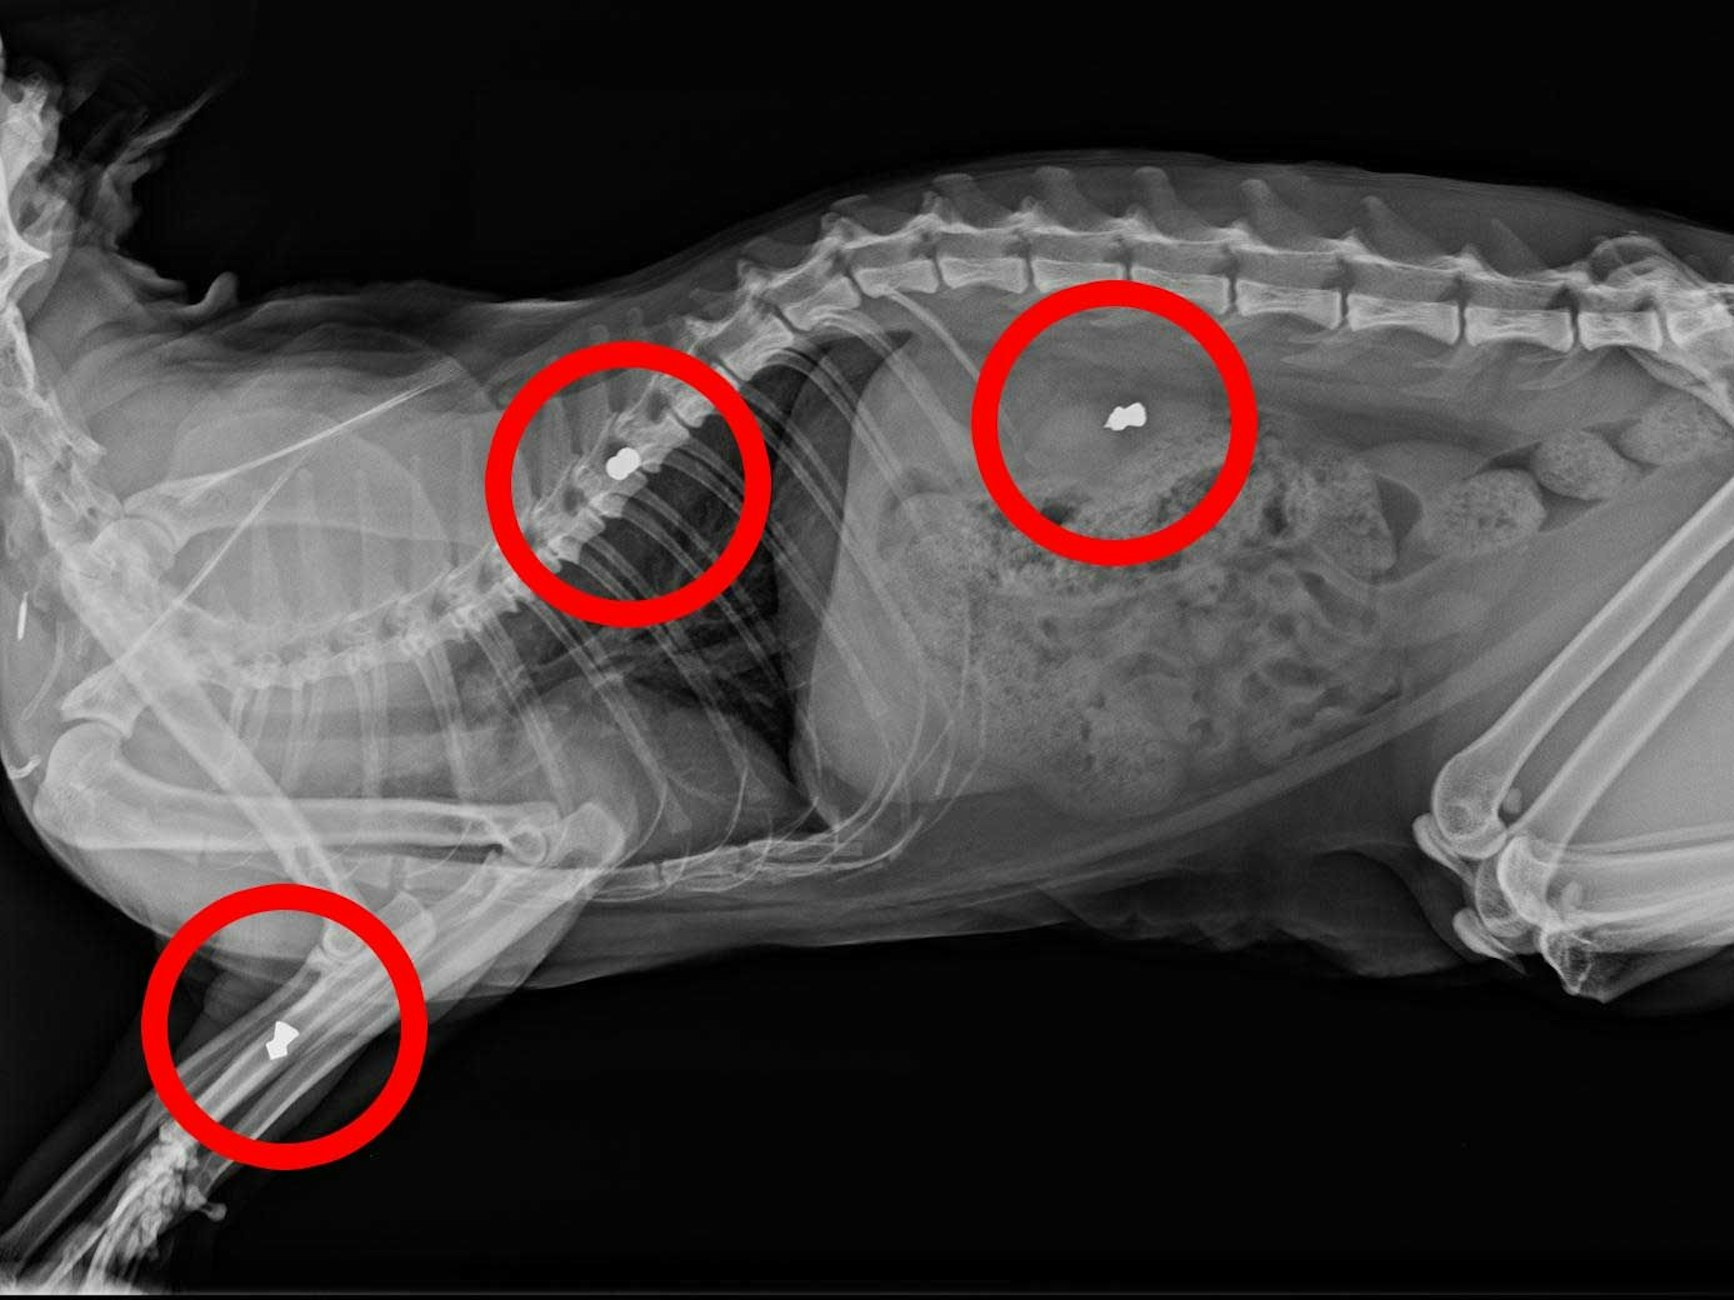

„So haben wir herausgefunden, dass dreimal auf Mr. Grey geschossen wurde. Der Knoten war ein Projektil“, erklärte der Tierarzt. Im Brustkorb, Rücken und Vorderbein stecken die Luftgewehr-Projektile. Sarah Bora stellte EXPRESS.de die Aufnahme zur Verfügung.

Das Röntgenbild von Kater Mr. Grey zeigt die drei Luftgewehr-Projektile, die im Körper stecken.